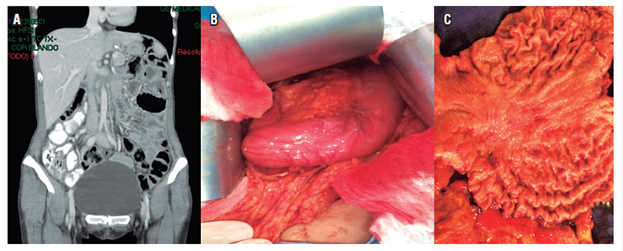

La paciente continuó con quimioterapia, con capecitabina y cisplatino. El día 16 de mayo, por decisión conjunta con la familia, se llevó a cirugía: se realizó la gastrectomía total con disección ganglionar D2. El resultado de patología fue el producto de gastrectomía total, adenocarcinoma gástrico de tipo difuso con células en anillo de sello, lesión de 6 x 5 cm, invasión tumoral hasta la grasa subserosa, invasión linfovascular y neural positivas, bordes proximal y distal libres de tumor, 5 de 17 ganglios positivos para compromiso tumoral, pT3pN2, epiplón negativo para tumor, rotulado diafragma izquierdo negativo para tumor, ganglios de la arteria hepática negativos para tumor, borde esofágico por aparte negativo para tumor y estado de HER2 negativo (Figura 3).

Figura 3 A. Tomografía de abdomen normal. B. Engrosamiento de las paredes de la región corporal gástrica. C. Pieza quirúrgica con lesión gástrica corporal.